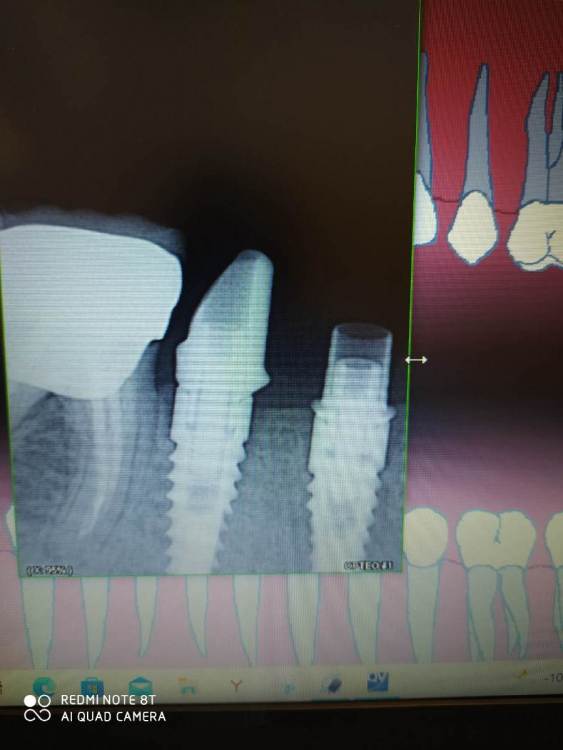

Evgen-Vozhd Опубликовано 17 ноября, 2021 Поделиться Опубликовано 17 ноября, 2021 Добрый день,коллеги. Пришла пациентка из другой клиники, не устроило качество коронок (был запах). Сделали новые абатменты и каркасы- они на фото. Прилегание абатментов к платформе на мой взгляд неплотное. Вопрос: это брак или у биогоризонта так и должно быть? Ссылка на комментарий

chervoncevdaniil Опубликовано 22 ноября, 2021 Поделиться Опубликовано 22 ноября, 2021 У вас все впорядке,на Xive похожая ситуация,при прикручивании супраструктуры есть на РГ эта точка,в области платформа и могут быть сомнения что досело или нет,мне даже как то хирург за это предъявлял,что я коронку недосадил,а потом я показал ему его рентген с формирователями десны где все тоже самое) Ссылка на комментарий

chervoncevdaniil Опубликовано 22 ноября, 2021 Поделиться Опубликовано 22 ноября, 2021 1 час назад, dentikl сказал: если все родное,БГ-в 0 садиться. Конечно в 0,но на вашем ренгене тоже есть РГ прозрачность как 2 точки по краям,это может многих смущать,на ксайфе так же. ПРи этом компоненты сидят четко,просто их конструктив такой. На израиле,например,такого нет Ссылка на комментарий

Evgen-Vozhd Опубликовано 24 ноября, 2021 Автор Поделиться Опубликовано 24 ноября, 2021 21.11.2021 в 18:44, dentikl сказал: Сделал снимок с оригинальной платформой Биогоризонт. Точности прилегания по платформе всё равно не вижу. Хз... ощущение, что щель между юбкой абатмента и платформой. Ссылка на комментарий

АнтонТЛТ Опубликовано 24 ноября, 2021 Поделиться Опубликовано 24 ноября, 2021 (изменено) 4 минуты назад, АнтонТЛТ сказал: Проекция снимка не правильная, но мезиальный выглядит докрученным. Дистальный не докручен. Ключём затягивали? Изменено 24 ноября, 2021 пользователем АнтонТЛТ Ссылка на комментарий

Evgen-Vozhd Опубликовано 24 ноября, 2021 Автор Поделиться Опубликовано 24 ноября, 2021 6 часов назад, АнтонТЛТ сказал: Ключём затягивали? Затянул 20н/см. Абатменты по ощущениям садятся как надо, без сопротивления при закручивании винта. только по снимку непонятки Ссылка на комментарий